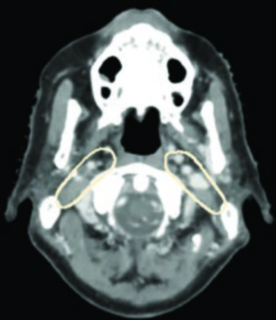

La experiencia del Memorial Sloan Kettering Cancer Center ilustra la aplicación práctica de estos volúmenes. En un caso T2N0 de seno piriforme izquierdo, el PET/TC reveló lesión captante extendiéndose hasta la línea media con el margen inferior aproximándose a la región postcricoidea. La RM T1 con gadolinio confirmó desplazamiento del pliegue ariepiglótico izquierdo sin diseminación definitiva a la supraglotis. La planificación con SIB incluyó PTV_6996 (enfermedad macroscópica), PTV_5940 (alto riesgo subclínico) y PTV_5610 (bajo riesgo), con cobertura bilateral de retrofaríngeos y retroestiloides, laringe completa desde hioides hasta cricoides, y niveles IV y VI por la extensión inferior tumoral.